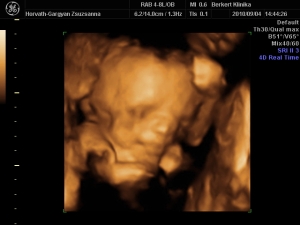

nagyon jó eltelt a szombatunk a drága férjemmel, későn keltünk, egy kis fincsi sült császár szalonnás reggeli tükör tojással...aztán takarítás, csodaszép idő volt ma...2-re mentünk a 4D-s uh-ra :!: :wink:

Valami fantasztikus volt :lol: annyira jól éreztük magunkat, Cipike annyira kis izgága babó, hogy alig lehetett követni mikor merre van, de sikerültek a képek és a DVD-s...egyszerűen nem tudunk vele betelni, már 2-szer megnéztük és még mindig ámulunk és bámulunk :!: :roll: :wink: Sztem az arca totál rám hasonlít, apácska el is volt keseredve :roll: :wink:

Minden a legnagyobb rendben van Cipikével, már 1140 g és csodaszép kis kukis :!: :wink:

És egy pár kép a 4D-ről...

Kép ARC

Kép KUKI, oda is van írva, csak a kicsinyítés miatt nem nagyon lehet elolvasni :!: :roll: :wink:

Kép MOSOLY